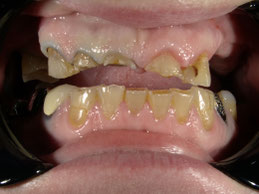

Ja, möglich! In diesem Fall mittels Kronen und Teleskop- prothese.

Ein gebrochener Zahn ist nicht nur schmerzhaft, sondern kann auch funktionelle und ästhetische Probleme verursachen. Ob durch einen Unfall, Zähneknirschen oder Karies – bei einem Zahnbruch ist schnelles Handeln entscheidend.

Emotionen bestimmen unser Leben. Psychischer Stress oder traumatische Erlebnisse beeinflussen unser Essverhalten und können zu Anorexie oder Bulimie führen. Dies kann nicht nur primär zu gesundheitlichen Problemen führen, sondern auch Ihr Lächeln beeinflussen. Bulimie z.B. kann zu starken Erosionen führen und so Ihren Zahnschmelz zerstören. Das macht Ihre Zähne dunkler, da sich unter dem Zahnschmelz eine dunklere Zahnschicht befindet. Allein durch Rekonstruktion des verlorenen Zahnschmelzes ist es hier nicht getan. Zunächst brauchen Sie professionelle Hilfe für das ursächliche Problem. Wenn Sie Ihr Selbstvertrauen und Selbstwertgefühl wieder gewonnen haben können Sie sich nun Ihrem Aussehen zuwenden.